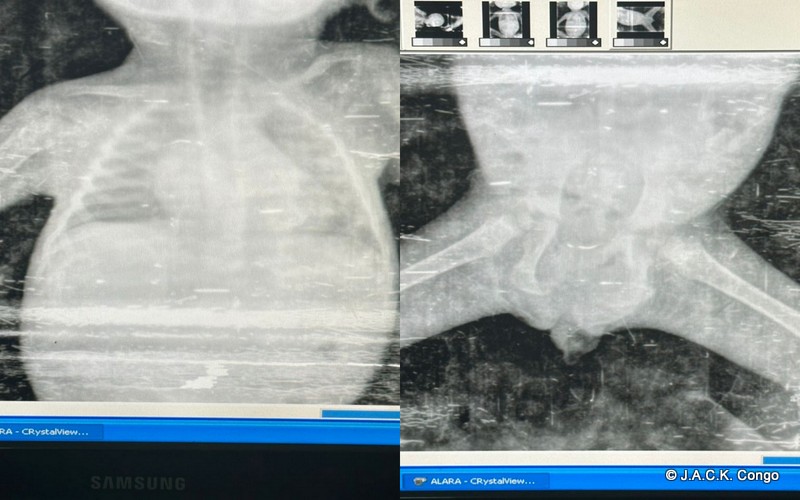

Quant au petit chimpanzé, vu son état de santé, des radios complètes de son corps s’imposaient. Nous avons pu découvrir avec horreur et stupéfaction que le jeune animal avait eu tout le côté droit blessé (l’omoplate fracturée ainsi qu’une double fracture fémorale) et que la calcification des ces fractures étaient toujours en cours.

Selon les vétérinaires consultés, il s’avère que la calcification au niveau de sa jambe a déformé son bassin et que, par conséquent, la petite Sana ne pourra jamais être mère c’est-à-dire qu’elle serait dans l’incapacité d’expulser un bébé toute seule. Il faudra d’office l’aider avec césarienne pour que son bébé soit viable mais qu’en sera-t-il si Sana sera relâchée dans un groupe en forêt sans contact ni assistance humaine?